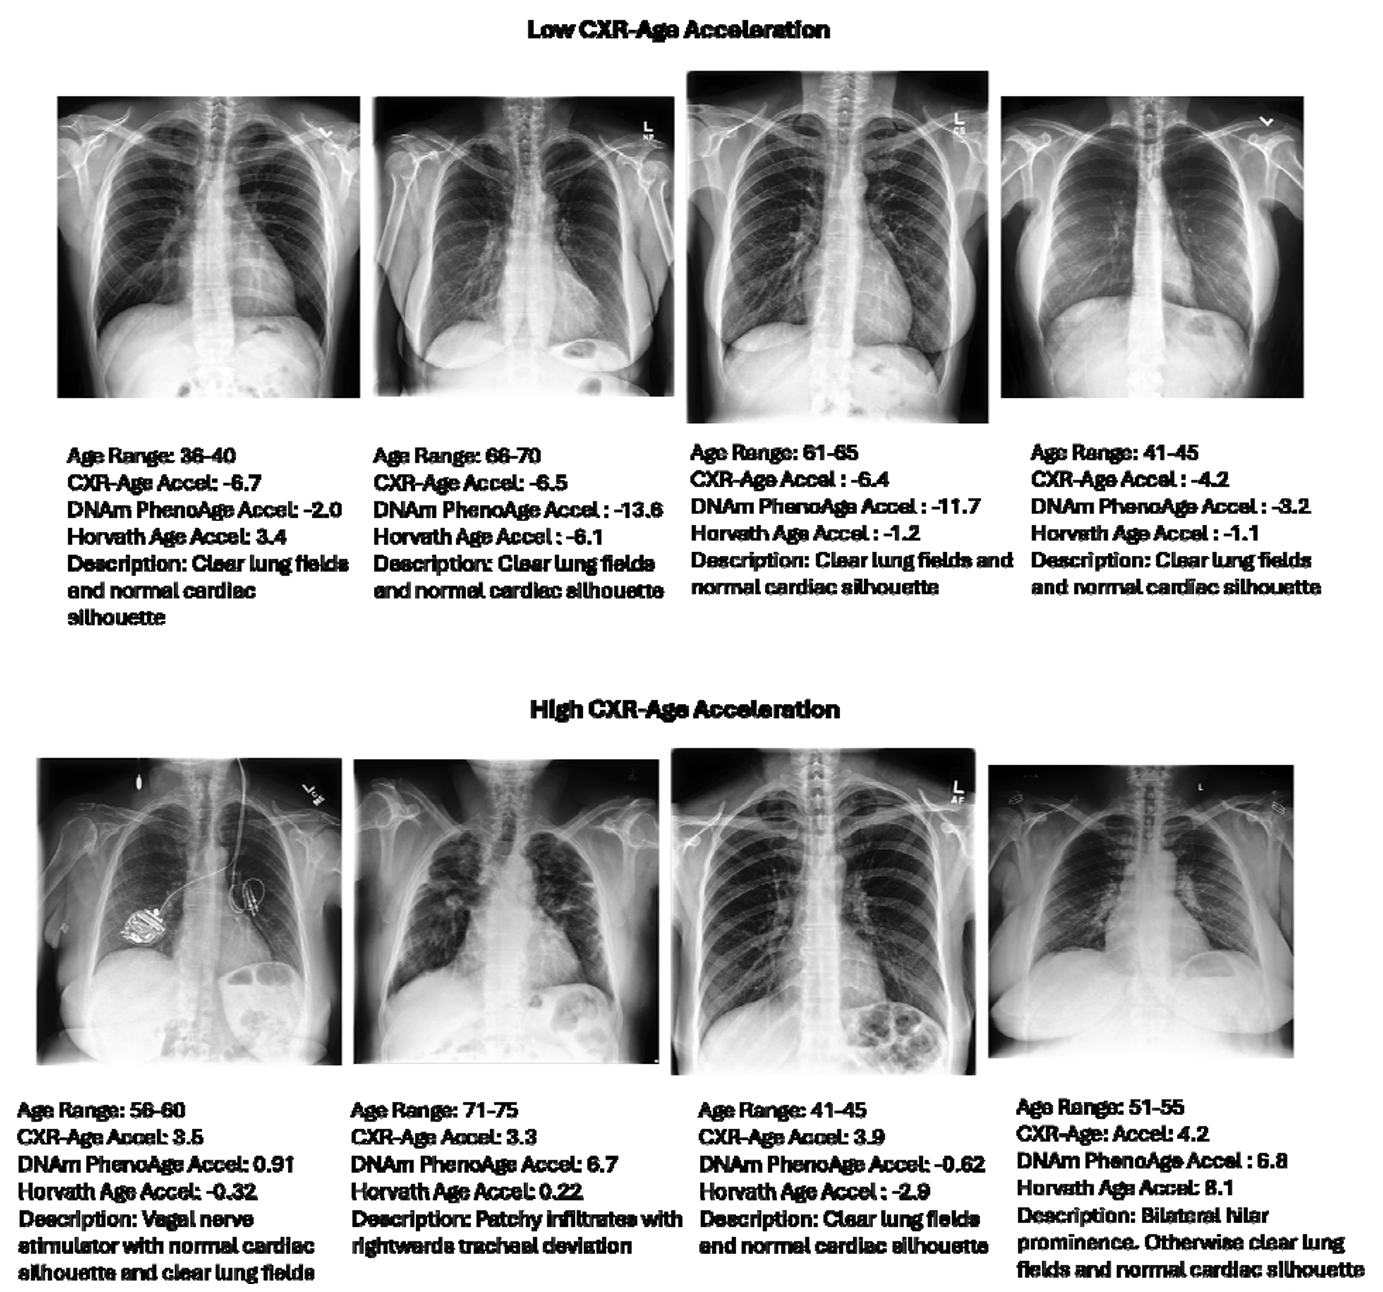

In addition to examining the link between CXR-Age and the two proteins, the team of researchers reported that they had radiologists review a series of X-rays ranging from very low to very high CXR-Age acceleration. The review of the X-rays from both directions highlighted some features observed on the lower CXR-Age X-ray series that consistently indicated clear lungs and normal sized hearts.

Conversely there were clear indicators of increased lung markings, thickened airways (indicating some form of respiratory disease), fluid build-up in the lungs, enlargement of the heart and/or lungs as observed by the radiologists in the CXR-Age X-rays with the scores. Therefore, these visible and abnormal features provided insight into how the CXR-Age forward-thinking model learns to identify these features.